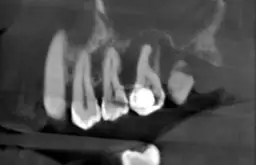

Korzeń zęba mlecznego jest kluczowym elementem jego budowy, umiejscowionym w dziąśle, w zębodołach kości szczęki lub żuchwy. Jego główną rolą jest stabilizacja zęba, co jest niezwykle ważne w procesie rozwoju uzębienia u dzieci. W porównaniu do korzeni zębów stałych, korzenie mleczaków są znacznie cieńsze i prostsze w budowie. Ich rozwój jest płytszy, co sprawia, że są bardziej podatne na uszkodzenia.

Korzenie zębów mlecznych są również słabo zmineralizowane, co zwiększa ryzyko ich zniszczenia, zwłaszcza w trakcie wymiany zębów. Proces resorpcji, który zachodzi podczas tego etapu, prowadzi do ich stopniowego znikania. Zrozumienie tych cech anatomicznych jest kluczowe dla rodziców, którzy chcą dbać o zdrowie jamy ustnej swoich dzieci oraz monitorować rozwój ich uzębienia.

Korzenie zębów mlecznych i stałych różnią się pod wieloma względami, co ma istotne znaczenie dla zdrowia jamy ustnej. Po pierwsze, korzenie zębów mlecznych są znacznie cieńsze i prostsze w budowie niż korzenie zębów stałych. Ich rozmiar jest mniejszy, co sprawia, że mają ograniczoną stabilność. Dodatkowo, korzenie mleczaków są słabiej zmineralizowane, co czyni je bardziej podatnymi na uszkodzenia i resorpcję.

Te różnice w budowie mają kluczowe znaczenie w kontekście wymiany uzębienia. W miarę jak zęby stałe rozwijają się i wywierają nacisk na korzenie zębów mlecznych, te ostatnie ulegają procesowi resorpcji, co prowadzi do ich zanikania. Zrozumienie tych różnic jest ważne, aby lepiej pojąć, jak rozwija się uzębienie dzieci.